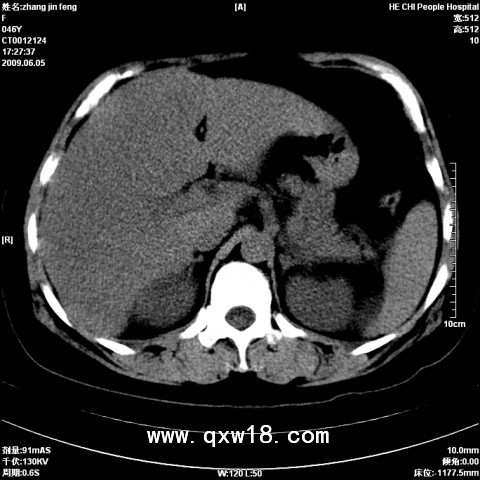

肝脏是人体重要的消化器官,对脂肪的消化、吸收、氧化、分解、合成、转运等起着十分重要的作用,并保持其动态平衡。脂肪在肝脏中产生堆积可以做一个形象的比喻,把肝脏比做一个加工车间,怎样会产生产品、原料的堆积呢?经验告诉我们:一是原料进的太多,超过车间的加工能力产生堆积;二是车间的工作效率下降产生堆积;三是产品不能及时运输出去也产生堆积。其实脂肪肝的形成也是这个道理。人体摄入的脂肪食物过量,肝脏代谢脂肪的功能下降或转运能力降低,人的活动量减少,脂肪消耗量减少,都会造成肝脏脂肪的堆积。脂肪肝,是指由于各种原因引起的肝细胞内脂肪堆积过多的病变。脂肪性肝病正严重威胁国人的健康,成为仅次于病毒性肝炎的第二大肝病。脂肪肝是一种常见的临床现象,而非一种独立的疾病。其临床表现轻者无症状,重者病情凶猛。一般而言,脂肪肝属可逆性疾病,早期诊断并及时治疗常可恢复正常。而眼前,也急需一种定量评估脂肪肝的诊断系统,用以脂肪肝患者的长期随访。就在广大脂肪肝患者苦恼之际,一种全新的、无创伤性的,能够实时、精确诊断脂肪肝分析检测诊断仪系统应运而生了。